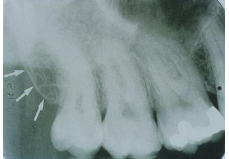

Maxillary Sinus

radiolucent area located above the apices of the premolar/molar areas in maxilla

(radiolucent)

Maxillary Tuberosity

radiopaque bulge distal to last tooth on max arch

(radiopaque)

Zygomatic Arch

J or U shaped radiopaque area superior to the maxillary 1st molar region